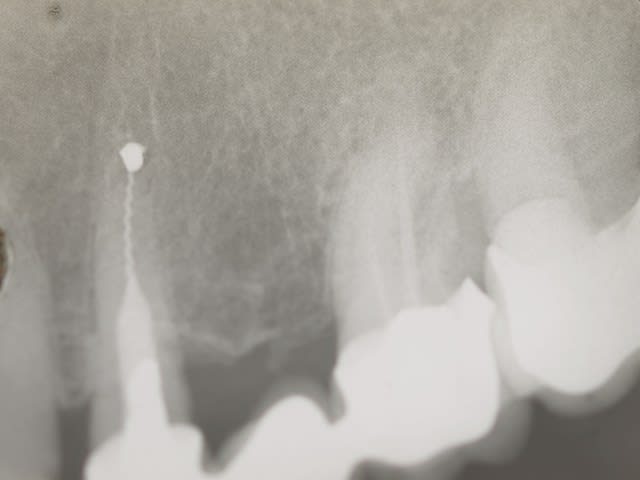

voila : depose du bridge a l arrache couronne depose de la racine coupe de la lime qui depasse amlgame a l apex repose racine et bridge dans la foulée

Avant  2  bvbppy - Eugenol

15 ans apres hlza61 - Eugenol

18/06/2014 à 18h42

C'est vrai que ça a l'air beaucoup mieux sans le bout qui dépasse...

Oui je veux bien parce que celle-là avec le gros lentulo qui reste dans la racine je trouve ça un peu couillu... Tu as fait ton obturation a retro avec quoi? Tu lui as fait directement un nouveau bridge ou tu as rescellé le vieux en contention le temps de la cicatrisation desmodontale?